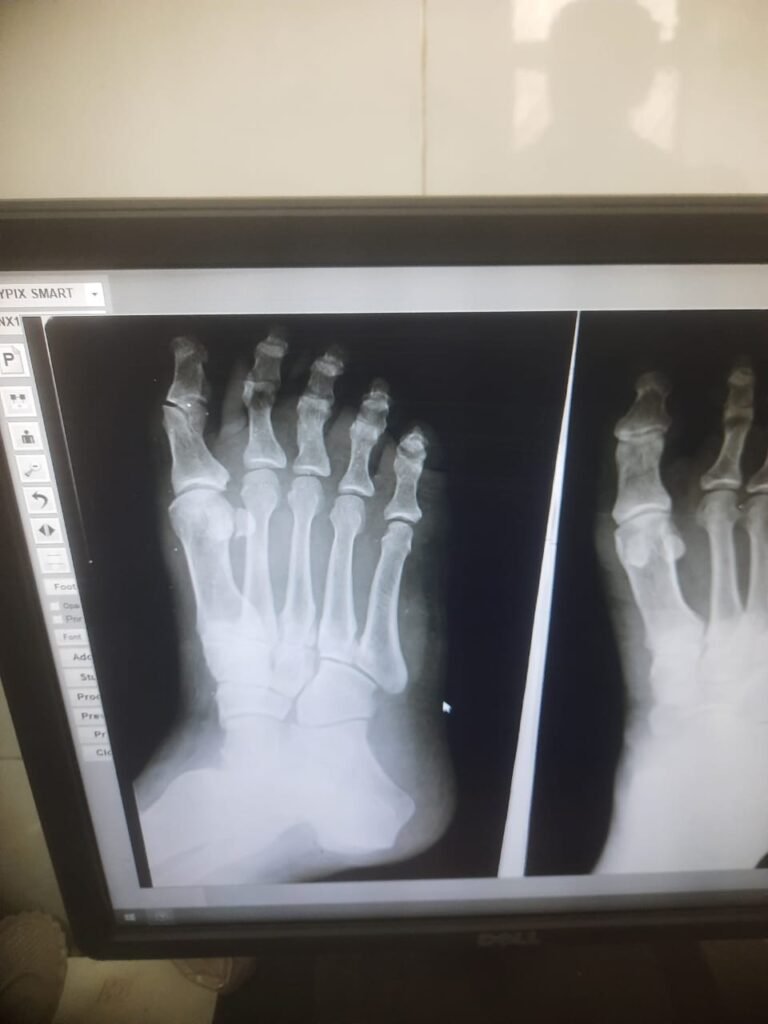

ऐसा ही मामला 31 तारीख का है उसे दिन इटारसी नरेंद्र नगर के निवासी महावीर बड़कुर जी अपनी पुत्री को को रेस्टोरेंट द पार्क में अपनी स्कूटी से छोड़ने जा रहे थे तभी उनकी स्कूटी रोड के मध्य में गैप में फंसने के पश्चात उनका ओवर ब्रिज पर एक्सीडेंट हुआ और स्कूटी भी क्षतिग्रस्त हो गई और ना ही कोई बीमा क्लेम मिला,, जिससे उनको पैरों में फ्रैक्चर अंदरुनी चोटे लगी हैं जिनका इलाज पूर्ण रूप से नहीं मिल पा रहा है और शहर के प्रतिष्ठित चिकित्सालयों ने आयुष्मान कार्ड से इलाज करने से मना कर दिया अब एक मध्यम वर्गीय रोज काम के खाने वाले शहर के नागरिक अपना इलाज शासकीय चिकित्सालय में ही करवा रहे है तत्कालीन स्थिति यह है कि अगर दोषी किसको ठहराया जाएगा तो किसे ,,ब्रिज बनाने वाले ठेकेदार को या पीडब्ल्यूडी के अधिकारी को या इलाज के नाम पर लूटने वाले शहर के प्रतिष्ठित डॉक्टरों को आखिर परेशान तो गरीब आदमी ही होता है जबकि उक्त नागरिक आयुष्मान कार्ड धारक है उसका इलाज शहर के किसी भी बड़े अस्पताल में भी हो सकता है लेकिन स्थिति यह है कि शहर में आयुष्मान के नाम पर जो लूट मची हुई है उसके मध्य नजर भी इलाज नहीं हो पा रहा है